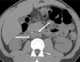

Rectal perforation

Rectal foreign bodies are large foreign items found in the rectum that can be assumed to have been inserted through the anus, rather than reaching the rectum via the mouth and gastrointestinal tract. It can be of clinical relevance if the patient cannot remove it the way they intended. [Source: Wikipedia ]